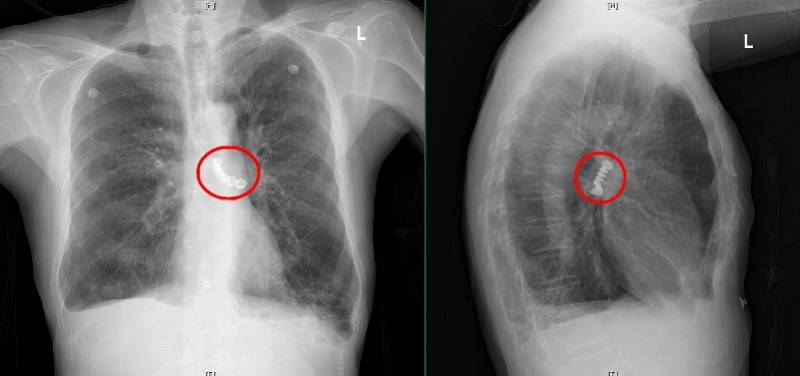

一个多月前 , 林小玲副主任医师接到一位特殊的患者 。 这位原就诊于该院妇科的44岁女性阿云(化名)两年多前患上了宫颈癌 , 并于近日不幸复发且出现了肺部转移 , 且在近一个月来病情恶化程度极快 。 考虑到患者明显的气促和呼吸困难症状 , 在胸部CT检查提示气管下段重度狭窄、右主支气管被肿瘤堵塞导致右肺几乎完全不张的情况下 , 患者被转入呼吸与危重症医学科进行治疗 。

阿云术前CT显示其气管下段重度狭窄、右主支气管被肿瘤堵塞导致右肺几乎完全不张(红圈处为气管仅剩的狭窄通路)